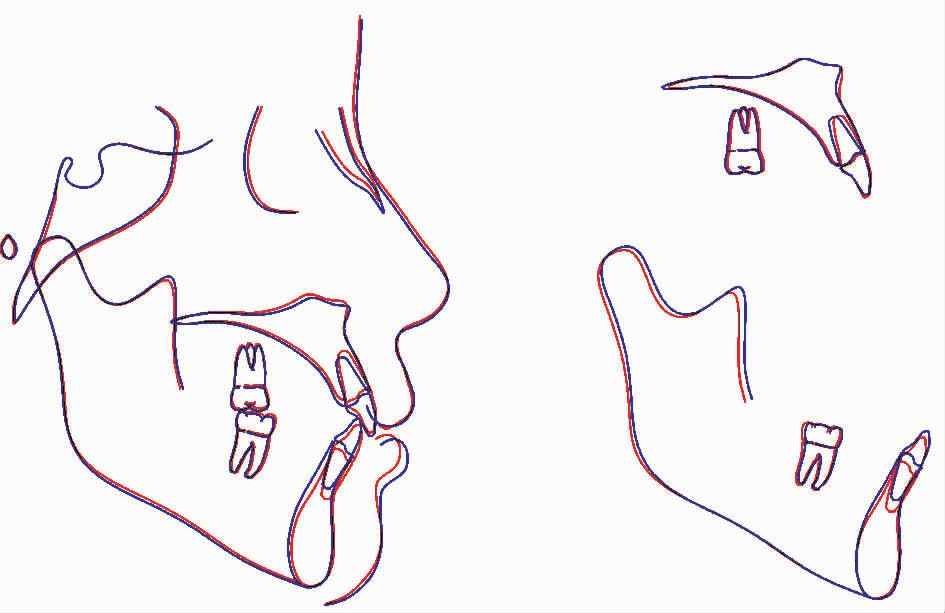

联合治疗结束后患者面型没有改变,双侧尖牙及磨牙为中性关系。下牙列排齐并压低,前牙覆(牙合)覆盖正常。双侧颞下颌关节未发现弹响及压痛。曲面断层片未见明显的下前牙牙根吸收。头影测量显示下前牙舌向移动并压低,下颌平面角没有明显的改变(图5)。

图5 病例矫治前后头影测量重叠图

图5 病例矫治前后头影测量重叠图